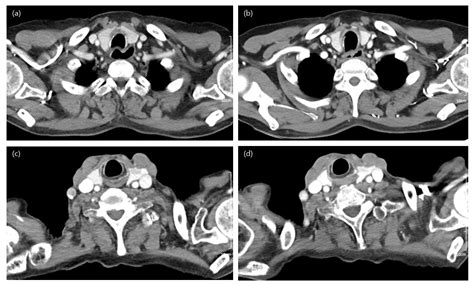

In the field of radiology, the density of tissues dictates how they appear on an x-ray image. Soft tissues and blood vessels often lack the necessary contrast to be seen distinctly without assistance. This is where Iodine Contrast proves invaluable. Because iodine has a high atomic number, it is highly efficient at absorbing x-rays, which causes those specific areas to appear bright white on a digital scan. This visual “pop” helps clinicians track blood flow, identify blockages, and characterize the margins of tumors or inflammation.

When injected into the bloodstream, the agent travels through the circulatory system, highlighting the arterial and venous anatomy. This is particularly crucial in emergency scenarios, such as detecting pulmonary embolisms or assessing internal bleeding after trauma. Furthermore, the substance is cleared by the kidneys, which provides a secondary benefit: the imaging process can simultaneously offer insights into how well the patient's renal system is functioning.